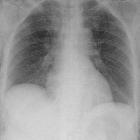

Weichteilemphysem nach Laparoskopie

Weichteilemphysem

nach Laparoskopie ohne Pneumothorax oder Mediastinalemphysem